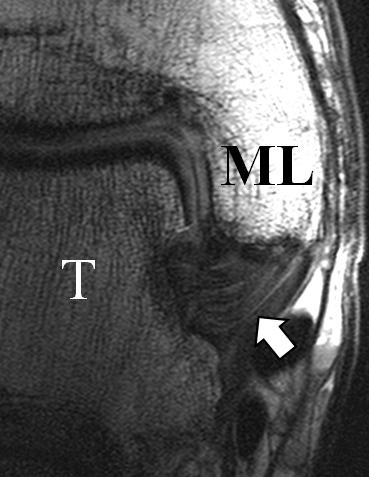

Zu Fehlinterpretationen eines intakten LFTA führt unter Umständen das unmittelbar kaudal des LFTA parallel verlaufende Ligamentum talocalcaneum laterale (Abb. 9 a). Dieses kann bei Verwendung von Schichtdicken um die 3 mm trotz Ruptur des LFTA durch Volumenteileffekte mit Anschnittsphänomenen einen intakten Bandverlauf vortäuschen.

Eine Ursache der falschen Diagnose einer LFTA-Ruptur ist die Fehlinterpretation der physiologische Bandlücke zwischen dem LFTA und der vorderen Syndesmose als traumatischer Banddefekt (Abb. 9 b).

Die Interpretation pathologischer Veränderungen sollte daher immer multiplanar unter Verwendung möglichst dünner Schichtdicken und hoher Ortsauflösungen erfolgen, um Fehldiagnosen zu vermeiden.